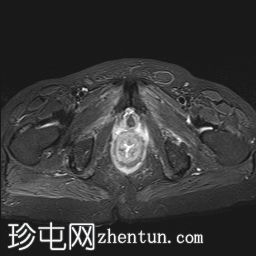

轴位

T2加权像

直肠下三分之一处可见一段弥漫性不规则肠壁增厚,伴浆膜外延伸,在右前外侧壁形成“C”形肿块,增强后呈不均匀强化,中央可见坏死。

左侧外侧壁和后壁可见大片缺损,内含气体和粪便,被不规则增厚的肠壁包裹。该缺损在T1加权像上呈低信号,在T2加权像上呈高信号,并伴有明显的扩散受限。

可见肠系膜脂肪间隙条索状改变和水肿。